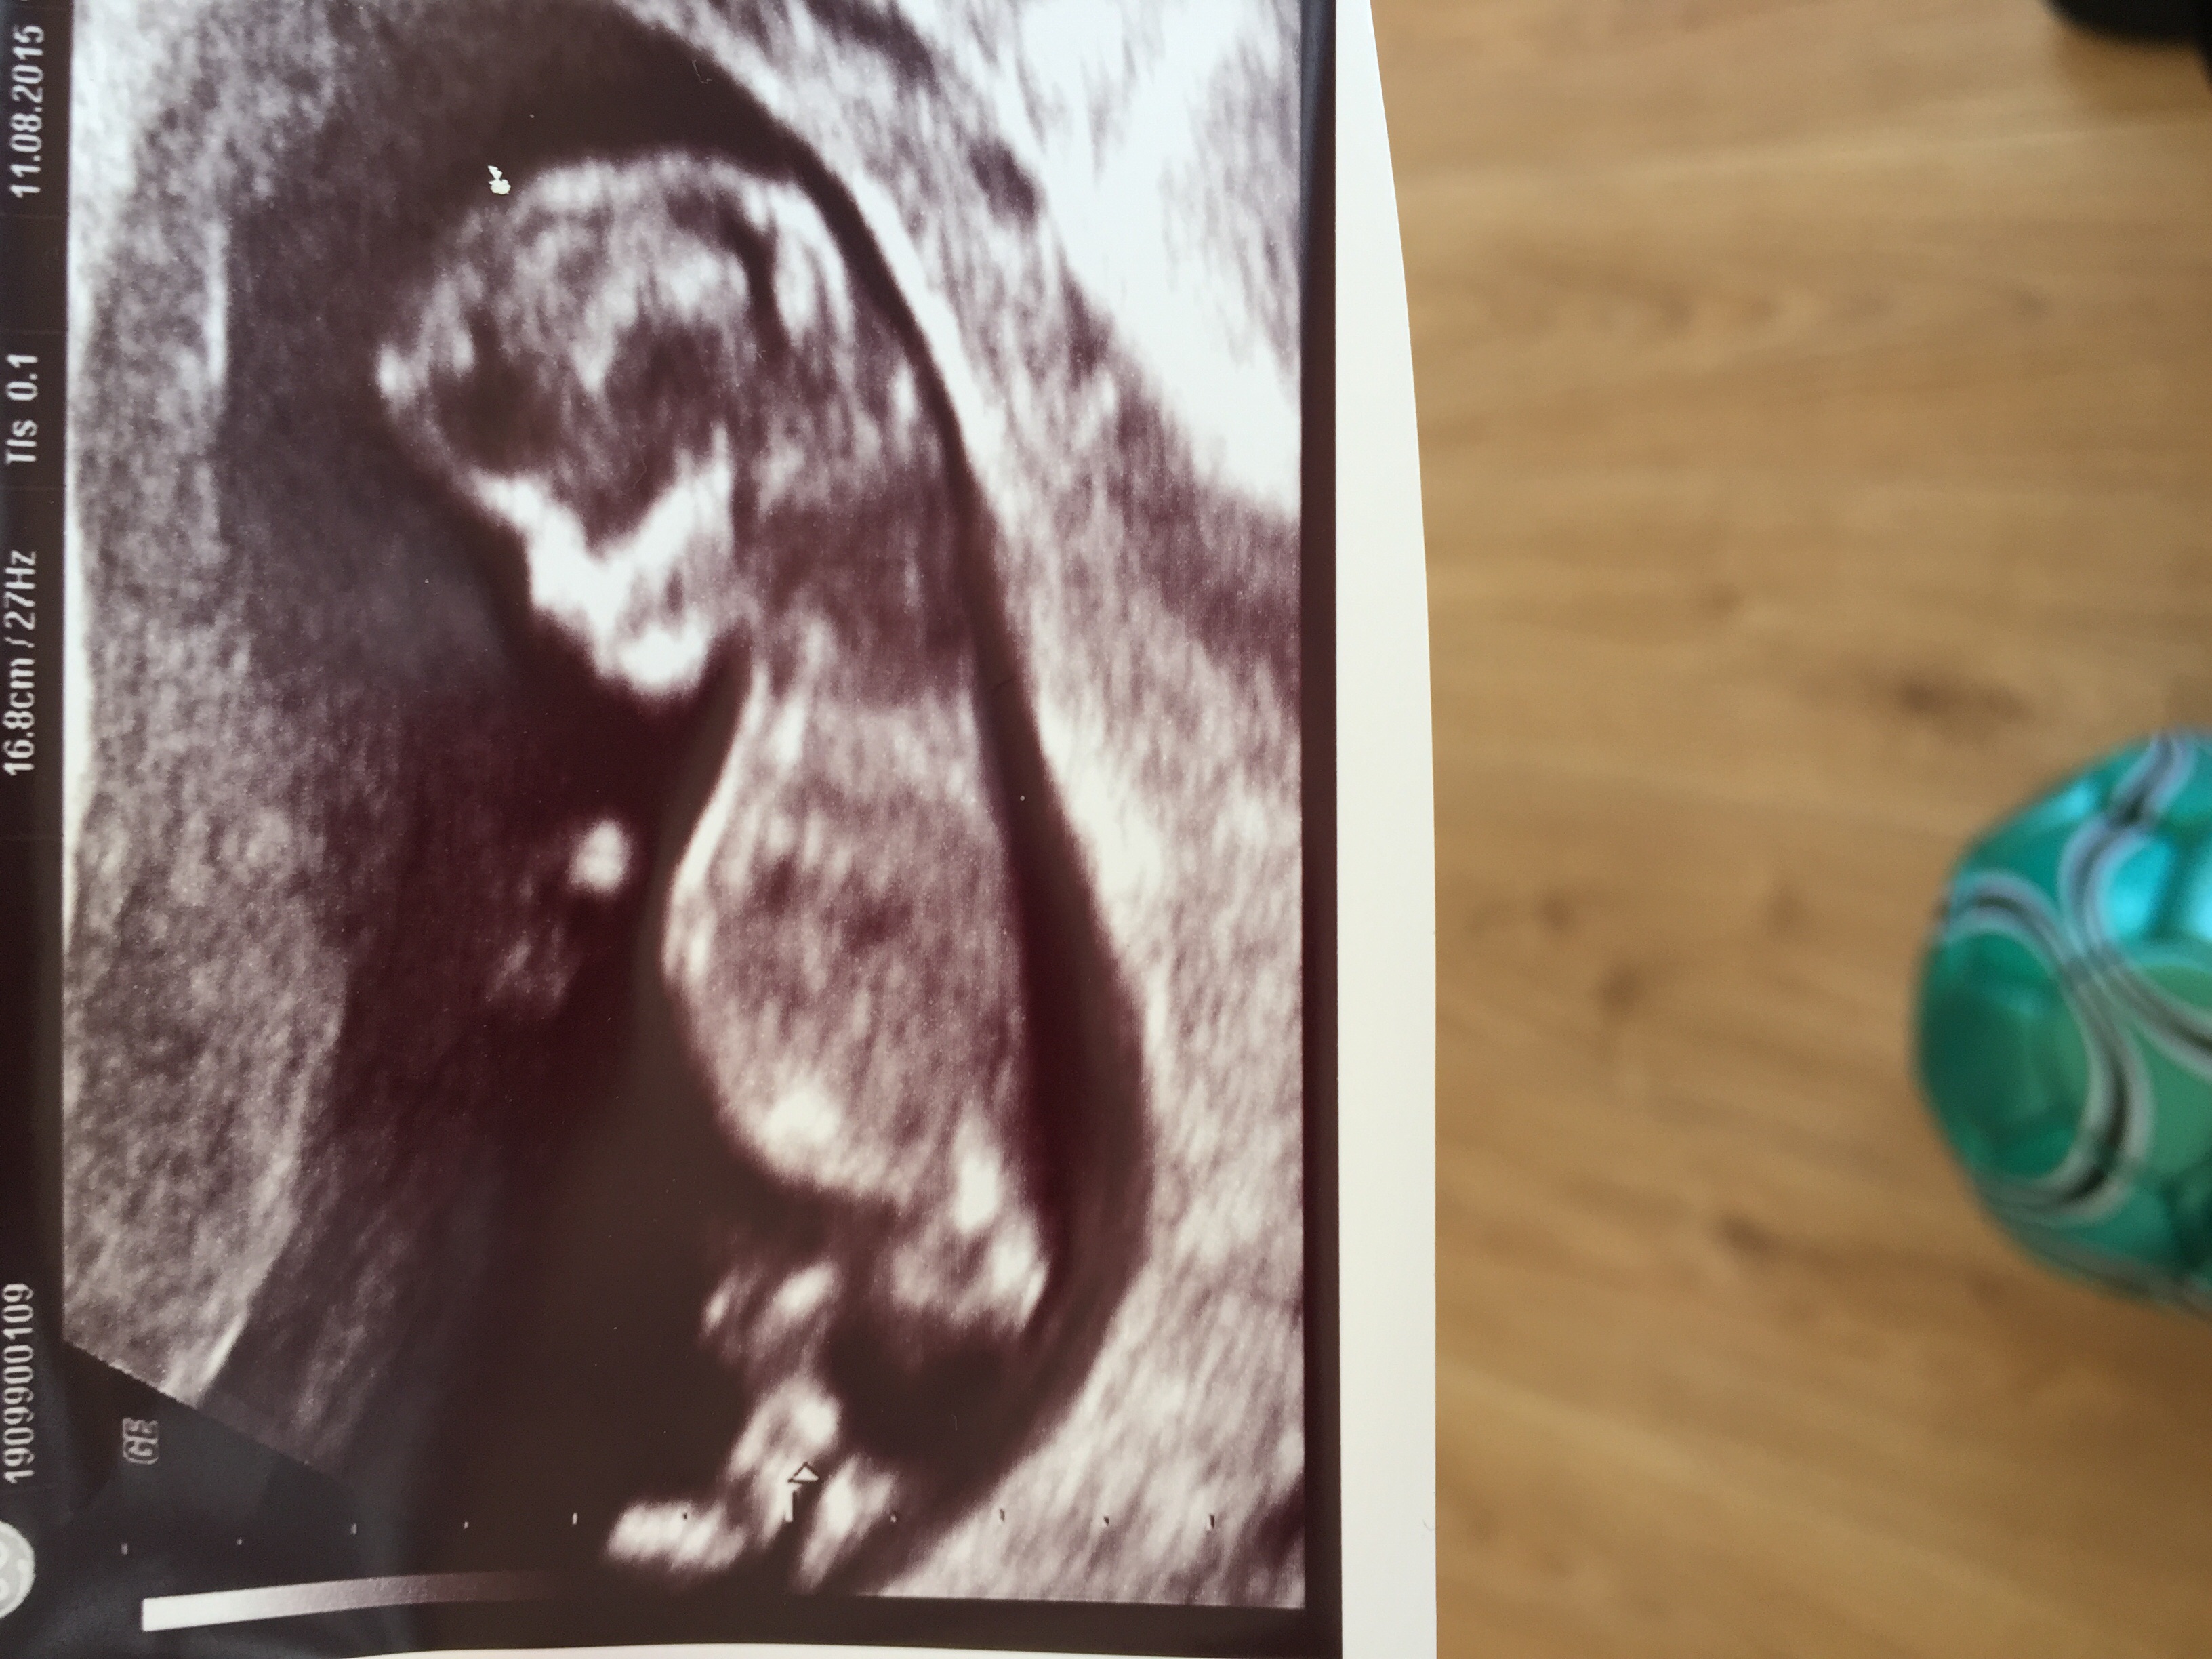

Attachment 26762Attachment 26762

This ones tricky but I'm leaning girl